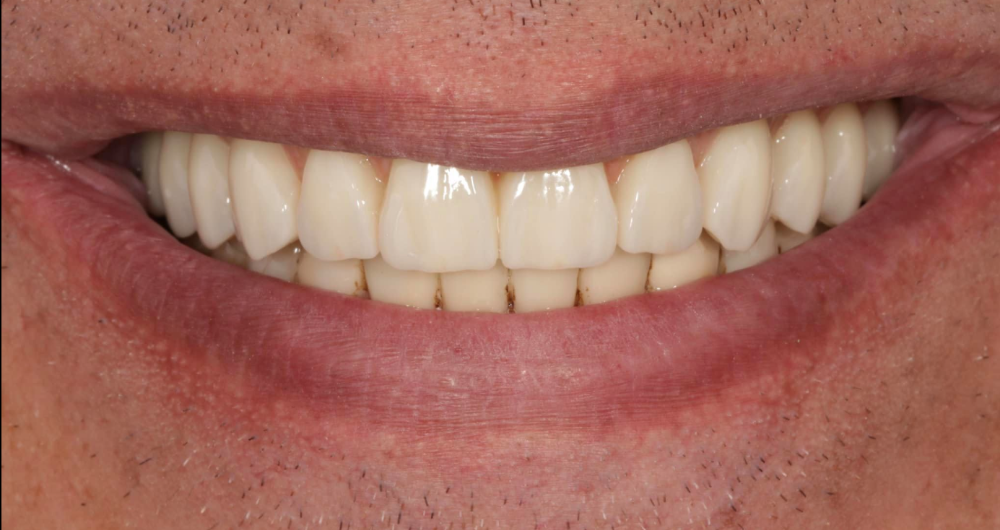

Používáme multivrstvý zirkon pro maximální estetiku, pevnost a dlouhou životnost.

- důraz na estetiku a přirozený úsměv

Výsledky, které mluví za vše

Ukázky práce před a po